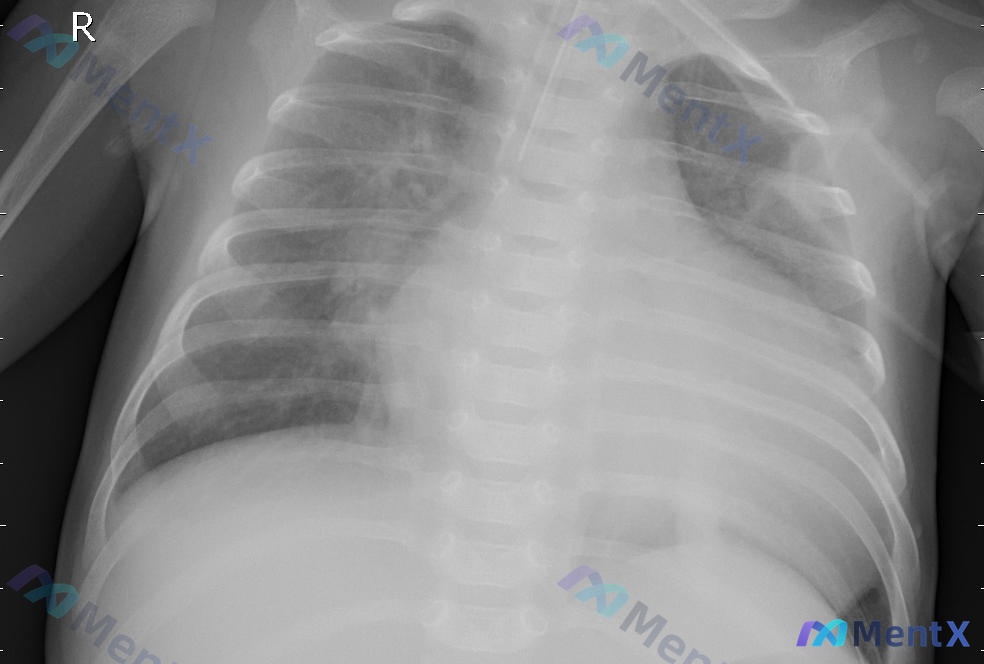

整理了一份胸部X光片的影像资料,核心表现很典型,但鉴别方向有点容易走偏: 核心影像表现 - 肺实质:右肺下野大片状密度增高影,边缘模糊,呈融合趋势,占据右下肺野大部分区域,局部肺纹理被掩盖;左肺野纹理稍增多 - 胸膜腔:右侧肋膈角变钝、闭锁;左侧肋膈角锐利 - 其他:气管纵隔居中,双侧肺门稍显饱满但...